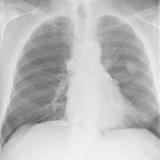

Case 1a

Thymoma